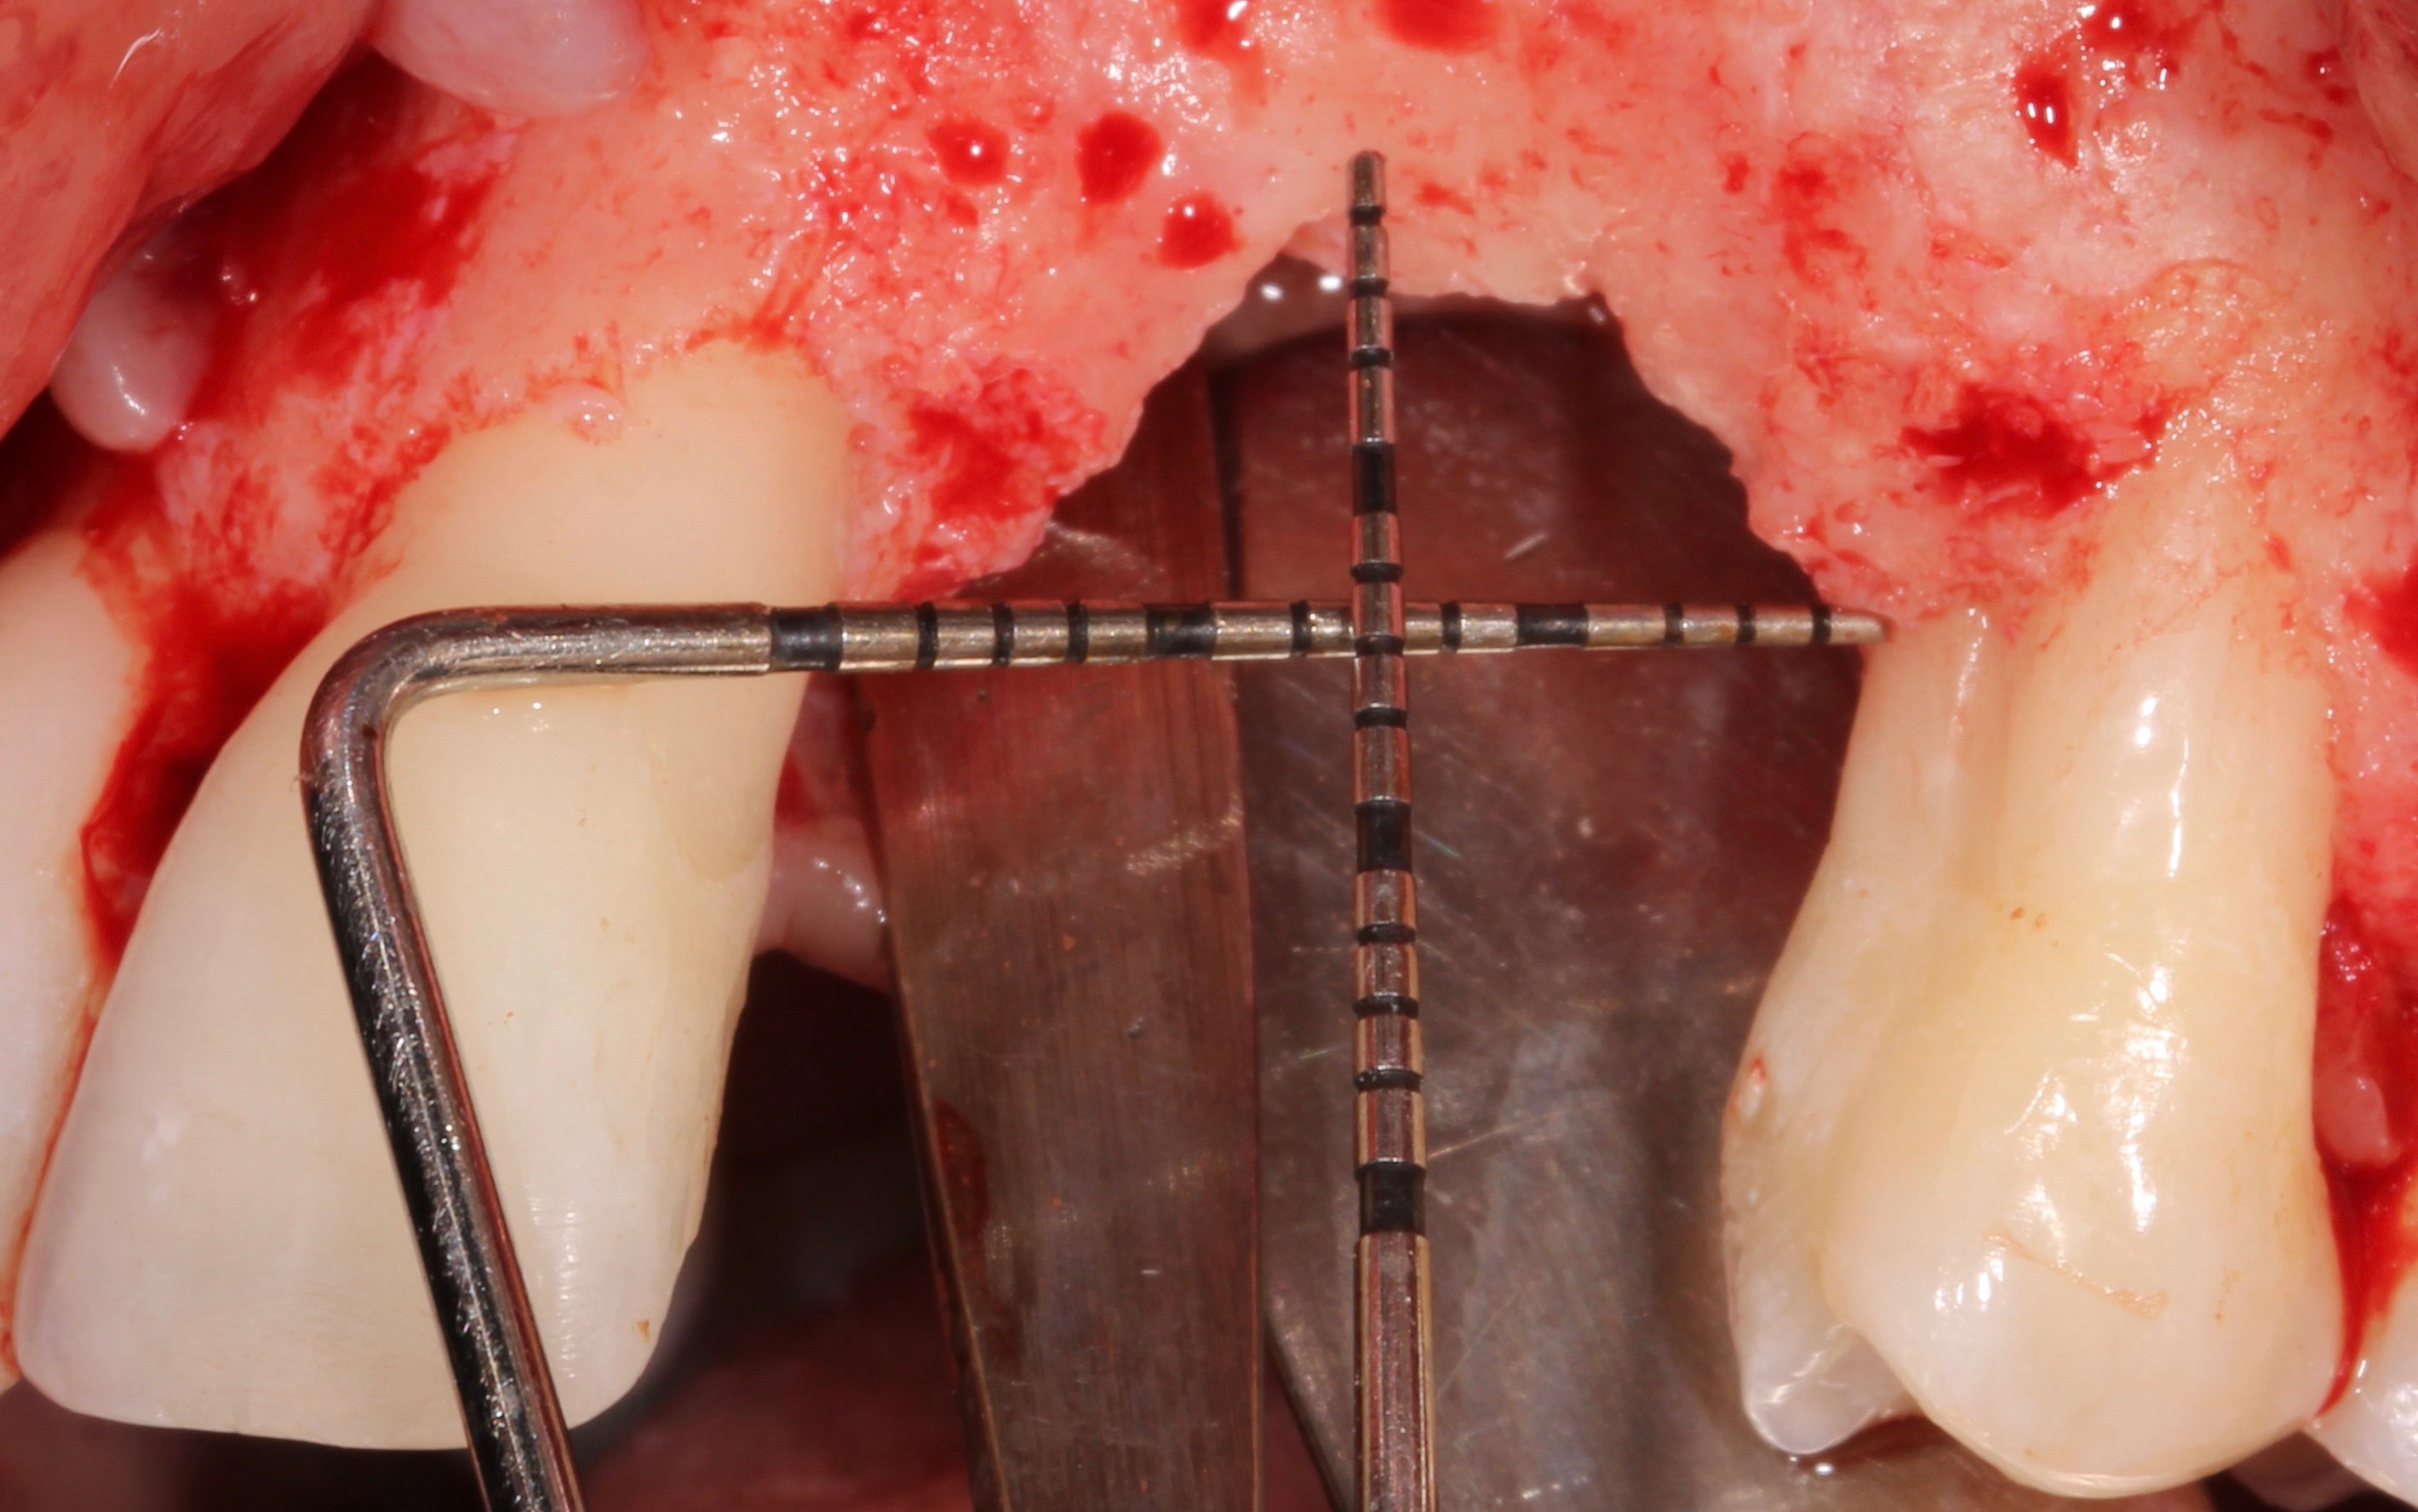

- 3 months later: (which turned out to be 2 years later because the patients was treated and failed elsewhere): 3D guided bone regeneration using 100% autogenous bone and a PTFE, Ti-reinforced NeoGen® membrane which was fixed by Neoss Tacks.

1 NeoGen Ti-Reinforced PTFE Membrane.